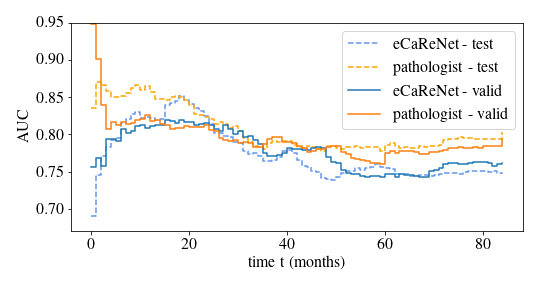

Furthermore, we compare eCaReNet to annotations of an expert pathologist. In clinical practice, pathologists do not estimate relapse times for patients directly, but assign a Gleason score. We compare eCaReNet’s discrimination power to the assigned ISUP scores, since a higher ISUP score corresponds to an increased risk of relapse. eCaReNet reaches on par performance in terms of AUC and c-index with the pathologist’s annotations on the validation set (AUC 0.78 and c-index 0.75). Only on the test set, the ISUP annotation shows higher AUC and c-index. In contrast to our model that uses a single TMA spot image per patient, for the ISUP annotation the whole prostate tissue was available, giving Gleason-based survival prediction an advantage over model-based prediction.

The d-calibration for eCaReNet is shown in \figurereffig:apd_result_dcal. The distribution’s uniformity has been confirmed with a chi-square test. The AUC of eCaReNet can also be evaluated over time, as shown in \figurereffig:auc_time.

fig:auc_time